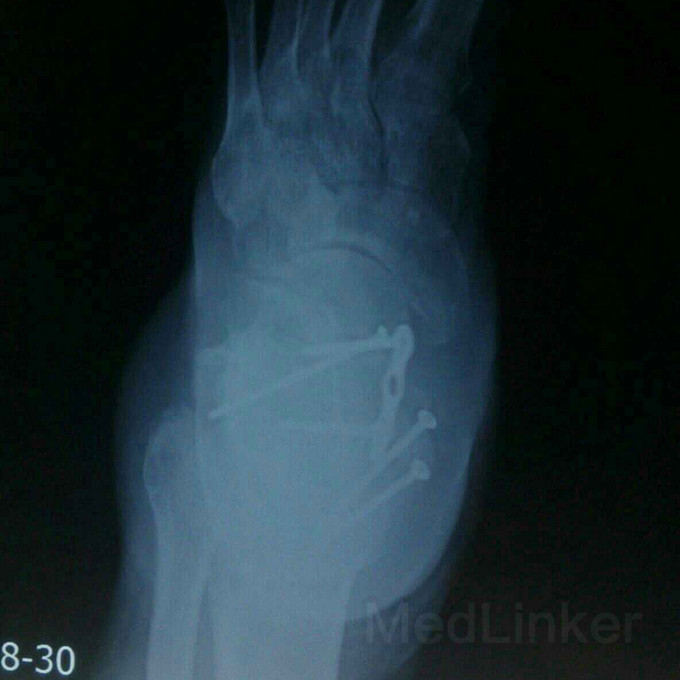

距骨术后一年余局部肿胀?

距骨骨折

外伤致右足距骨骨折,行钢板内固定术后半年余,现右足肿胀,影响行走,踝关节无法活动,该用什么办法好